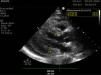

A 41-year-old woman with humoral deficiency and monoclonal gammopathy IgG lambda presented to the ER with fever and weakness and was diagnosed with an influenza A-related respiratory infection. Twenty-four hours later, she was admitted to the intensive care unit because of severe hypotension, requiring norepinephrine up to 0.5 μg/kg/min, hypoalbuminemia, and hemoconcentration. She was diagnosed with systemic capillary leak syndrome (SCLS) with intramyocardial edema (IME). SCLS is a condition characterized by the leakage of plasma and proteins into the interstitial compartment. It is associated with monoclonal gammopathy, and often occurs after an upper respiratory tract infection, with IME being a rare complication in this disease. In our patient, the transthoracic echocardiogram (TTE) performed at admission revealed that left ventricle ejection fraction (LVEF) was at the lower normal limit (LVEF 50%-55%) with restrictive physiology and evidence of diffuse myocardial thickening, as shown in the TTE images: parasternal long-axis view (Fig. 1 and Video A), parasternal short-axis view at apical level (Fig. 2), and apical four-chamber view (Fig. 3). This thickering was likely due to IME, since a TTE performed 1 month earlier showed normal myocardial thickness (Fig. 4, parasternal long-axis view). Treatment with immunoglobulins and corticosteroids was prescribed, but unfortunately, the patient died 24 hours after admission due to refractory shock.